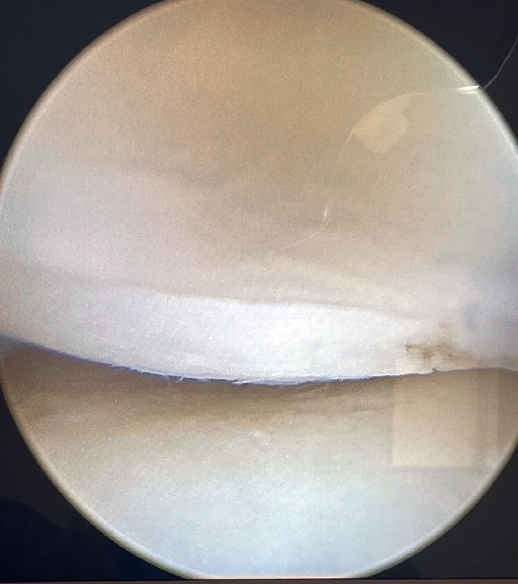

If tension is now applied to both sutures and we observe from the posterolateral portal, the radiocapitellar joint is seen to close following plication (Figure 8).